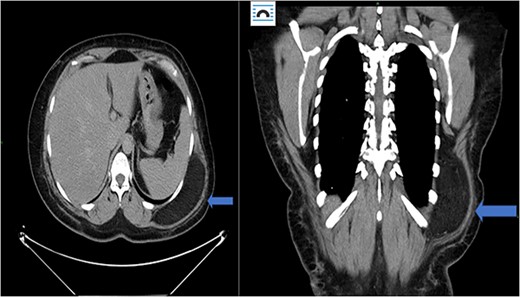

A 32-year-old female presented to the clinic with a palpable soft tissue back mass noticed a month prior to her visit. The patient had not noticed any change in size. On physical examination, a minimally mobile painless soft tissue mass was palpated and located on the left side of the back. No skin changes were noted. The mass was ~13 × 15 cm on palpation. No punctate, drainage nor erythema were noted. The mass was not attached to the skin. Ultrasound was performed 20 days prior to her visit and detailed a large soft tissue mass at the site of clinical concern in the patient’s back on the left side measuring 10.5 × 8.5 × 3.3 cm. Ultrasound-guided core biopsy was performed under local anesthetic in the office setting and demonstrated a Lobulated tumor composed of a mixture of cell types in varying proportions with small, bland, central nuclei, polygonal cells with granular eosinophilic cytoplasm and multivacuolated cells with numerous lipid droplets. Some univacuolated adipocytes were identified. Medium-sized prominent stromal vessels were noticed. Mitotic figures were rare. A computed tomography (CT) scan of chest with contrast was performed to estimate the relationship of the mass to adjacent anatomical structures. The CT scan showed 12.6 × 10 × 3.9 cm lipomatous mass beneath the latissimus dorsi muscle along posterolateral aspect of upper abdomen/lower thorax favoring an intramuscular lipoma (Fig. 3). Patient agreed to have complete excision of the mass. After excision in the operating room, the specimen was sent to pathology and showed a well-circumscribed 266 gm fatty mass that was serially sectioned revealing homogenous yellow adipose tissue on cut section (Fig. 2). The specimen was submitted per grossing protocol which is one section per 1 cm. Final pathology confirmed diagnosis of hibernoma (Fig. 1).

Case 1: CT (axial and coronal view), blue arrow marks hibernoma.